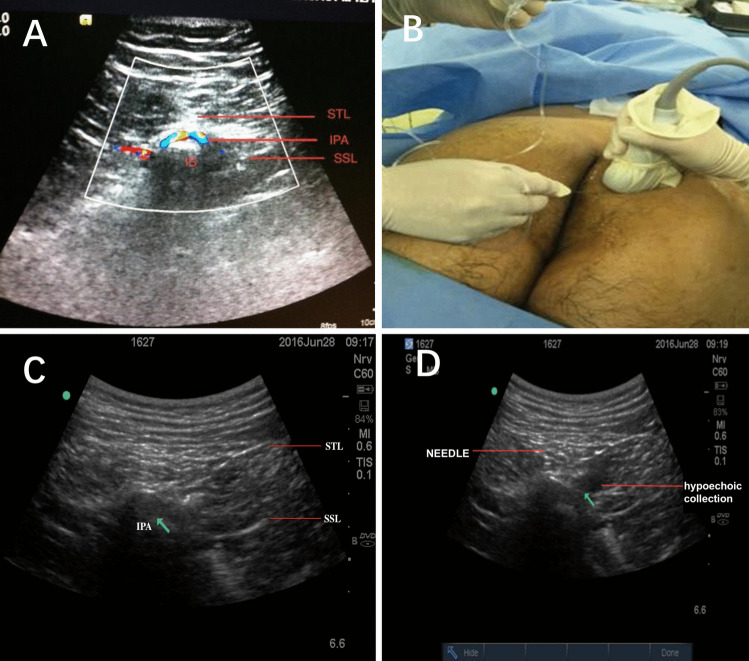

Purpose: The study aimed to evaluate the efficacy of ultrasound-guided pudendal nerve block (PNB) versus local anesthetic infiltration (LAI) in managing the pain.

Methods: This is a prospective, randomized, double-blinded trial, 78 patients undergoing procedure for prolapse and hemorrhoids (PPH) were randomly allocated to receive either ultrasound-guided PNB or LAI. Primary outcomes were postoperative pain scores using the visual analogue scale at multiple time points within the first 48 h. Secondary outcomes included tramadol consumption, incidence of postoperative nausea and vomiting, and quality of recovery-15 (QoR-15) scores.